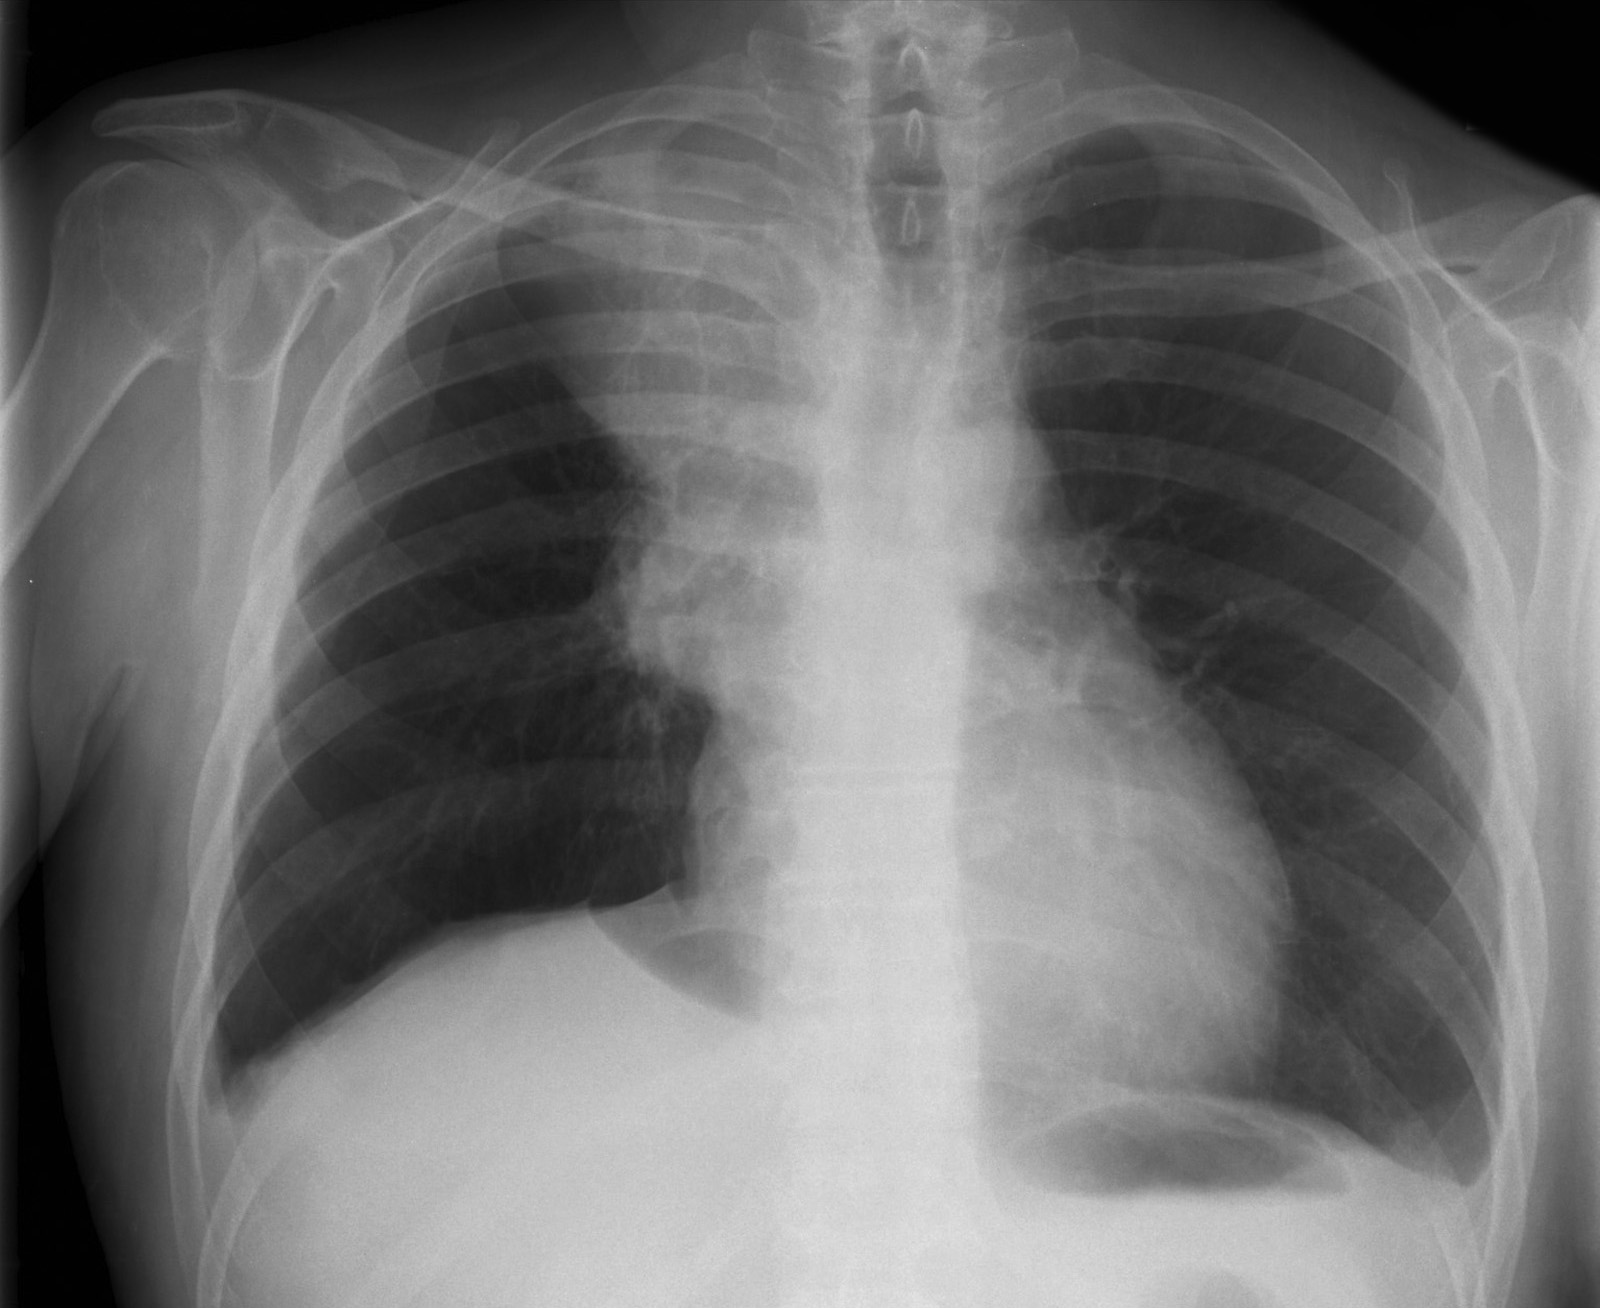

Снимок легких при туберкулезе является важным методом диагностики этого заболевания. На рентгеновских снимках можно увидеть изменения в легких, которые свойственны туберкулезу.

Фотографии снимков легких при туберкулезе

В данной статье представлены многочисленные фотографии снимков легких при туберкулезе, чтобы помочь вам понять, как выглядят изменения легких на рентгеновских снимках при этом заболевании.